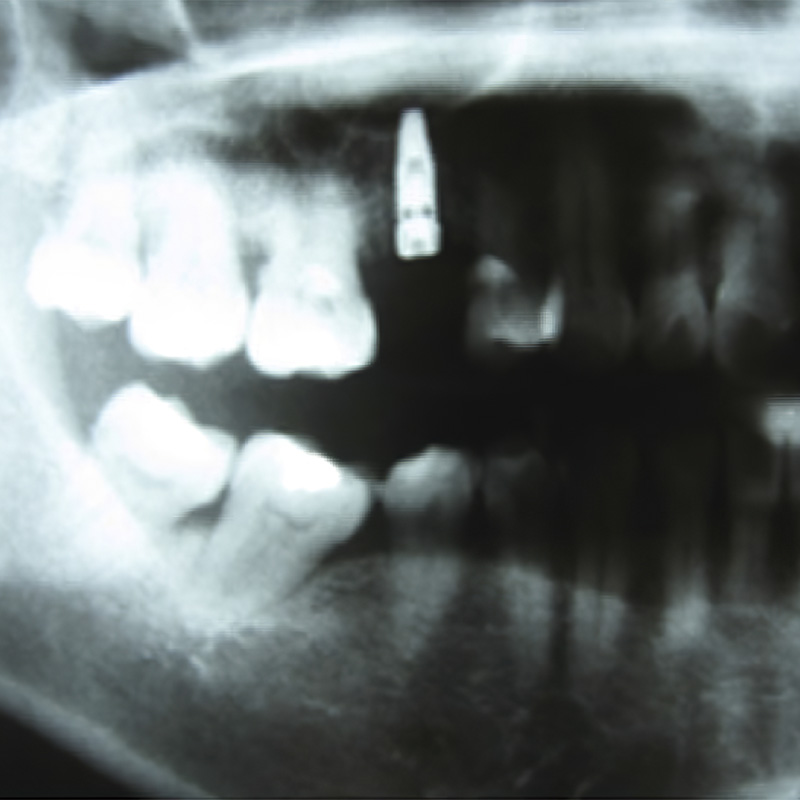

First mandible reconstruction with Osteomesh shaped tray to hold autologous bone grafts. Bony ingrowth and remodeling observed at 2 and 5 months postoperatively.

2019

First customized Osteopore (OSX) implant for orbital floor reconstruction.